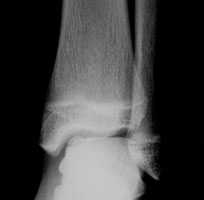

а. рентгенограмма голеностопа. - КТ. Метод, позволяющие понять, какую структуру имеют остеофиты. Также помогает в обнаружении патологии на начальной стадии, когда рентгенологической картины может быть недостаточно для постановки диагноза.

а. на рентгенограммах артроз голеностопного сустава, б. на КТ голеностопного сустава некроз таранной кости.